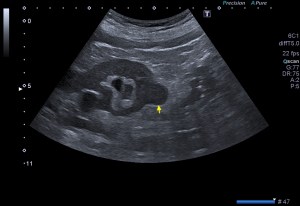

La radiografía revela aumento de las partes y se refrenda en la ecografía como puedes ver en la imagen aunque aún no hay afectación en el hueso en el caso que te presento hoy.

Ecografícamente y debido a su levedad, en el caso de hoy solo observamos cambios en las partes blandas de la cara lateral de la cabeza del quinto metatarsiano, este tejido se muestra heterogéneo, la cortical del hueso ligeramente prominente sin afectación de la misma.